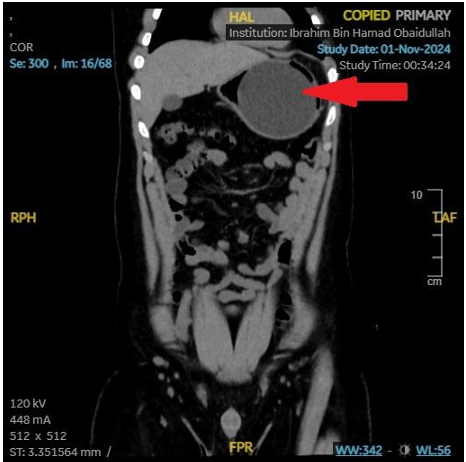

Hematopoietic stem cell transplantation (HSCT) is an essential therapy for malignant and non-malignant hematologic, autoimmune, and genetic disorders. However, post-transplant complications, particularly pulmonary infections, remain a leading cause of morbidity and mortality. Case report: We present the case of a 70-year-old male with chronic lymphocytic leukemia (CLL) who underwent allogeneic HSCT several years ago. Post-transplant, he received intravenous immunoglobulin (IVIG) every six weeks for immune support. Despite this, he developed chronic obstructive pulmonary disease (COPD) without any smoking history and has experienced recurrent pneumonia requiring frequent hospitalizations. Extensive microbiologic and imaging evaluations repeatedly failed to identify a causative organism. The patient remains on chronic antibiotic therapy, nebulized bronchodilators, and antiviral prophylaxis with valacyclovir. This case underscores the vulnerability of post-HSCT patients to recurrent, often unexplained pulmonary infections despite ongoing prophylactic and supportive measures. Management focuses on infection prevention and treatment through broad-spectrum antimicrobials, immunoglobulin replacement, and respiratory support, while addressing physical, psychological, and nutritional needs. Discussion: In patients with CLL and T-cell-depleted HSCT, persistent immunodeficiency can lead to refractory pulmonary complications, significantly reducing quality of life and survival. Early recognition, aggressive management, and multidisciplinary care are essential to improving outcomes in this high-risk population.